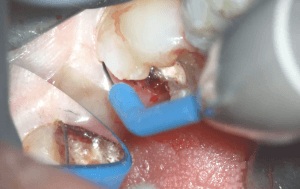

電気メスによる遠心歯肉の止血処理

遠心の歯肉は歯質のマージンが歯肉縁下となっているためマージンを明瞭に出ししっかり止血することが重要となります。

そのため電気メスにて歯肉切除と凝固を行っています。インレー修復による間接修復で印象をとる場合でも歯質のマージンが歯肉縁下となる場合は電気メスによる歯肉切除を行い窩洞のマージンをきれいに出す必要があるでしょう。